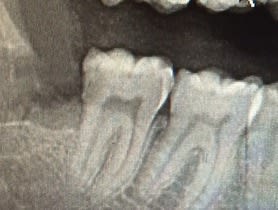

( la 47 est plus abimée en clinique et sur une rétro que sur la pano).

Tu ne connais pas le praticien qui parle ici, tu ne sais rien de lui ni du patient hormis une pano (qui est, comme chacun le sait, un très mauvais examen pour juger d'un plan de traitement). Tu n'as pas non plus vu l'état de la 48, pas plus que tu n'as vu la rétroalvéolaire ou la situation clinique, et tu n'as strictement aucune idée des tarifs du confrère, mais malgré ça tu te permets de juger le plan de traitement, les indications posées et les honoraires demandés !

4) Je me suis permis d'agrandir la pano , tu penses toujours que ca merite 40 euros ?